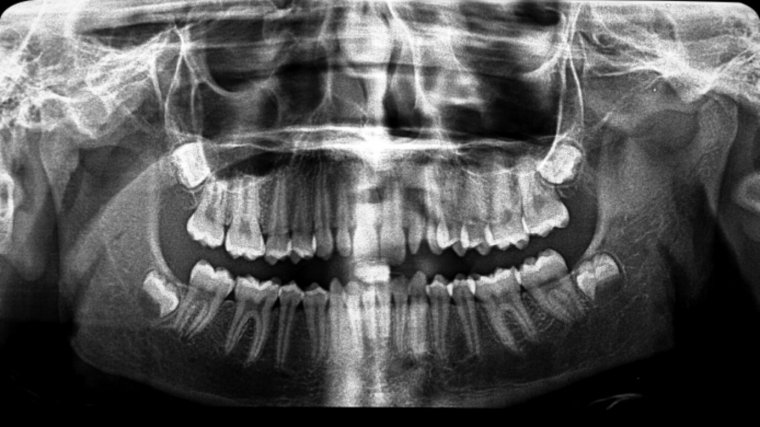

Existen muchísimas formas y tamaños de dientes diferentes en el mundo. Sin embargo, en ocasiones, algunas de las personas desarrollan unas piezas dentales fuera de lo común. Cuando se produce una alteración en el tamaño de los dientes, hablaremos de microdoncia y macrodoncia.

A pesar de que es difícil determinar cuándo existe una alteración, se establece que existe una anomalía cuando la proporción entre los dientes y el maxilar o mandíbula (es decir, la estructura donde se implantan los dientes) no es adecuada.

Las anomalías en tamaño de las piezas dentales son conocidas, según su tamaño, por macrodoncia, dientes más grandes de lo normal, o bien, microdoncia, dientes más pequeños de lo normal, es decir, en relación a la morfología de sus maxilares, su boca y su rostro en general.

La microdoncia se divide en localizada o parcial, y la microdoncia generalizada, según el número de dientes afectados. La más común es la parcial, que se da cuando uno presenta microdoncia solo en algunas piezas en concreto. Normalmente, los dientes más afectados son los incisivos superiores (dientes más anteriores), ya sea uno o los dos.

En el caso de la microdoncia generalizada, todos los dientes presentan un tamaño inferior de lo normal, lo que se puede dar en el enanismo hipofisiario. Un problema distinto, es cuando las piezas son pequeñas en relación al maxilar, debido al gran tamaño de este, y por ello, se aprecian unos dientes pequeños.

La macrodoncia se clasifica según el número de dientes afectados como, parcial o localizada y total. En la macrodoncia parcial, se encuentran afectados determinados dientes, éstos presentan una forma de mayor tamaño y/o con deformidad coronal (parte visible del diente). Los terceros molares inferiores (muelas del juicio inferiores) son los dientes que mayormente presentan macrodoncia. Por otro lado, la macrodoncia generalizada se da cuando se trata de varios dientes que tienen aspecto grande respecto el resto de la dentadura, un hecho que sucede en el gigantismo hipofisiario.